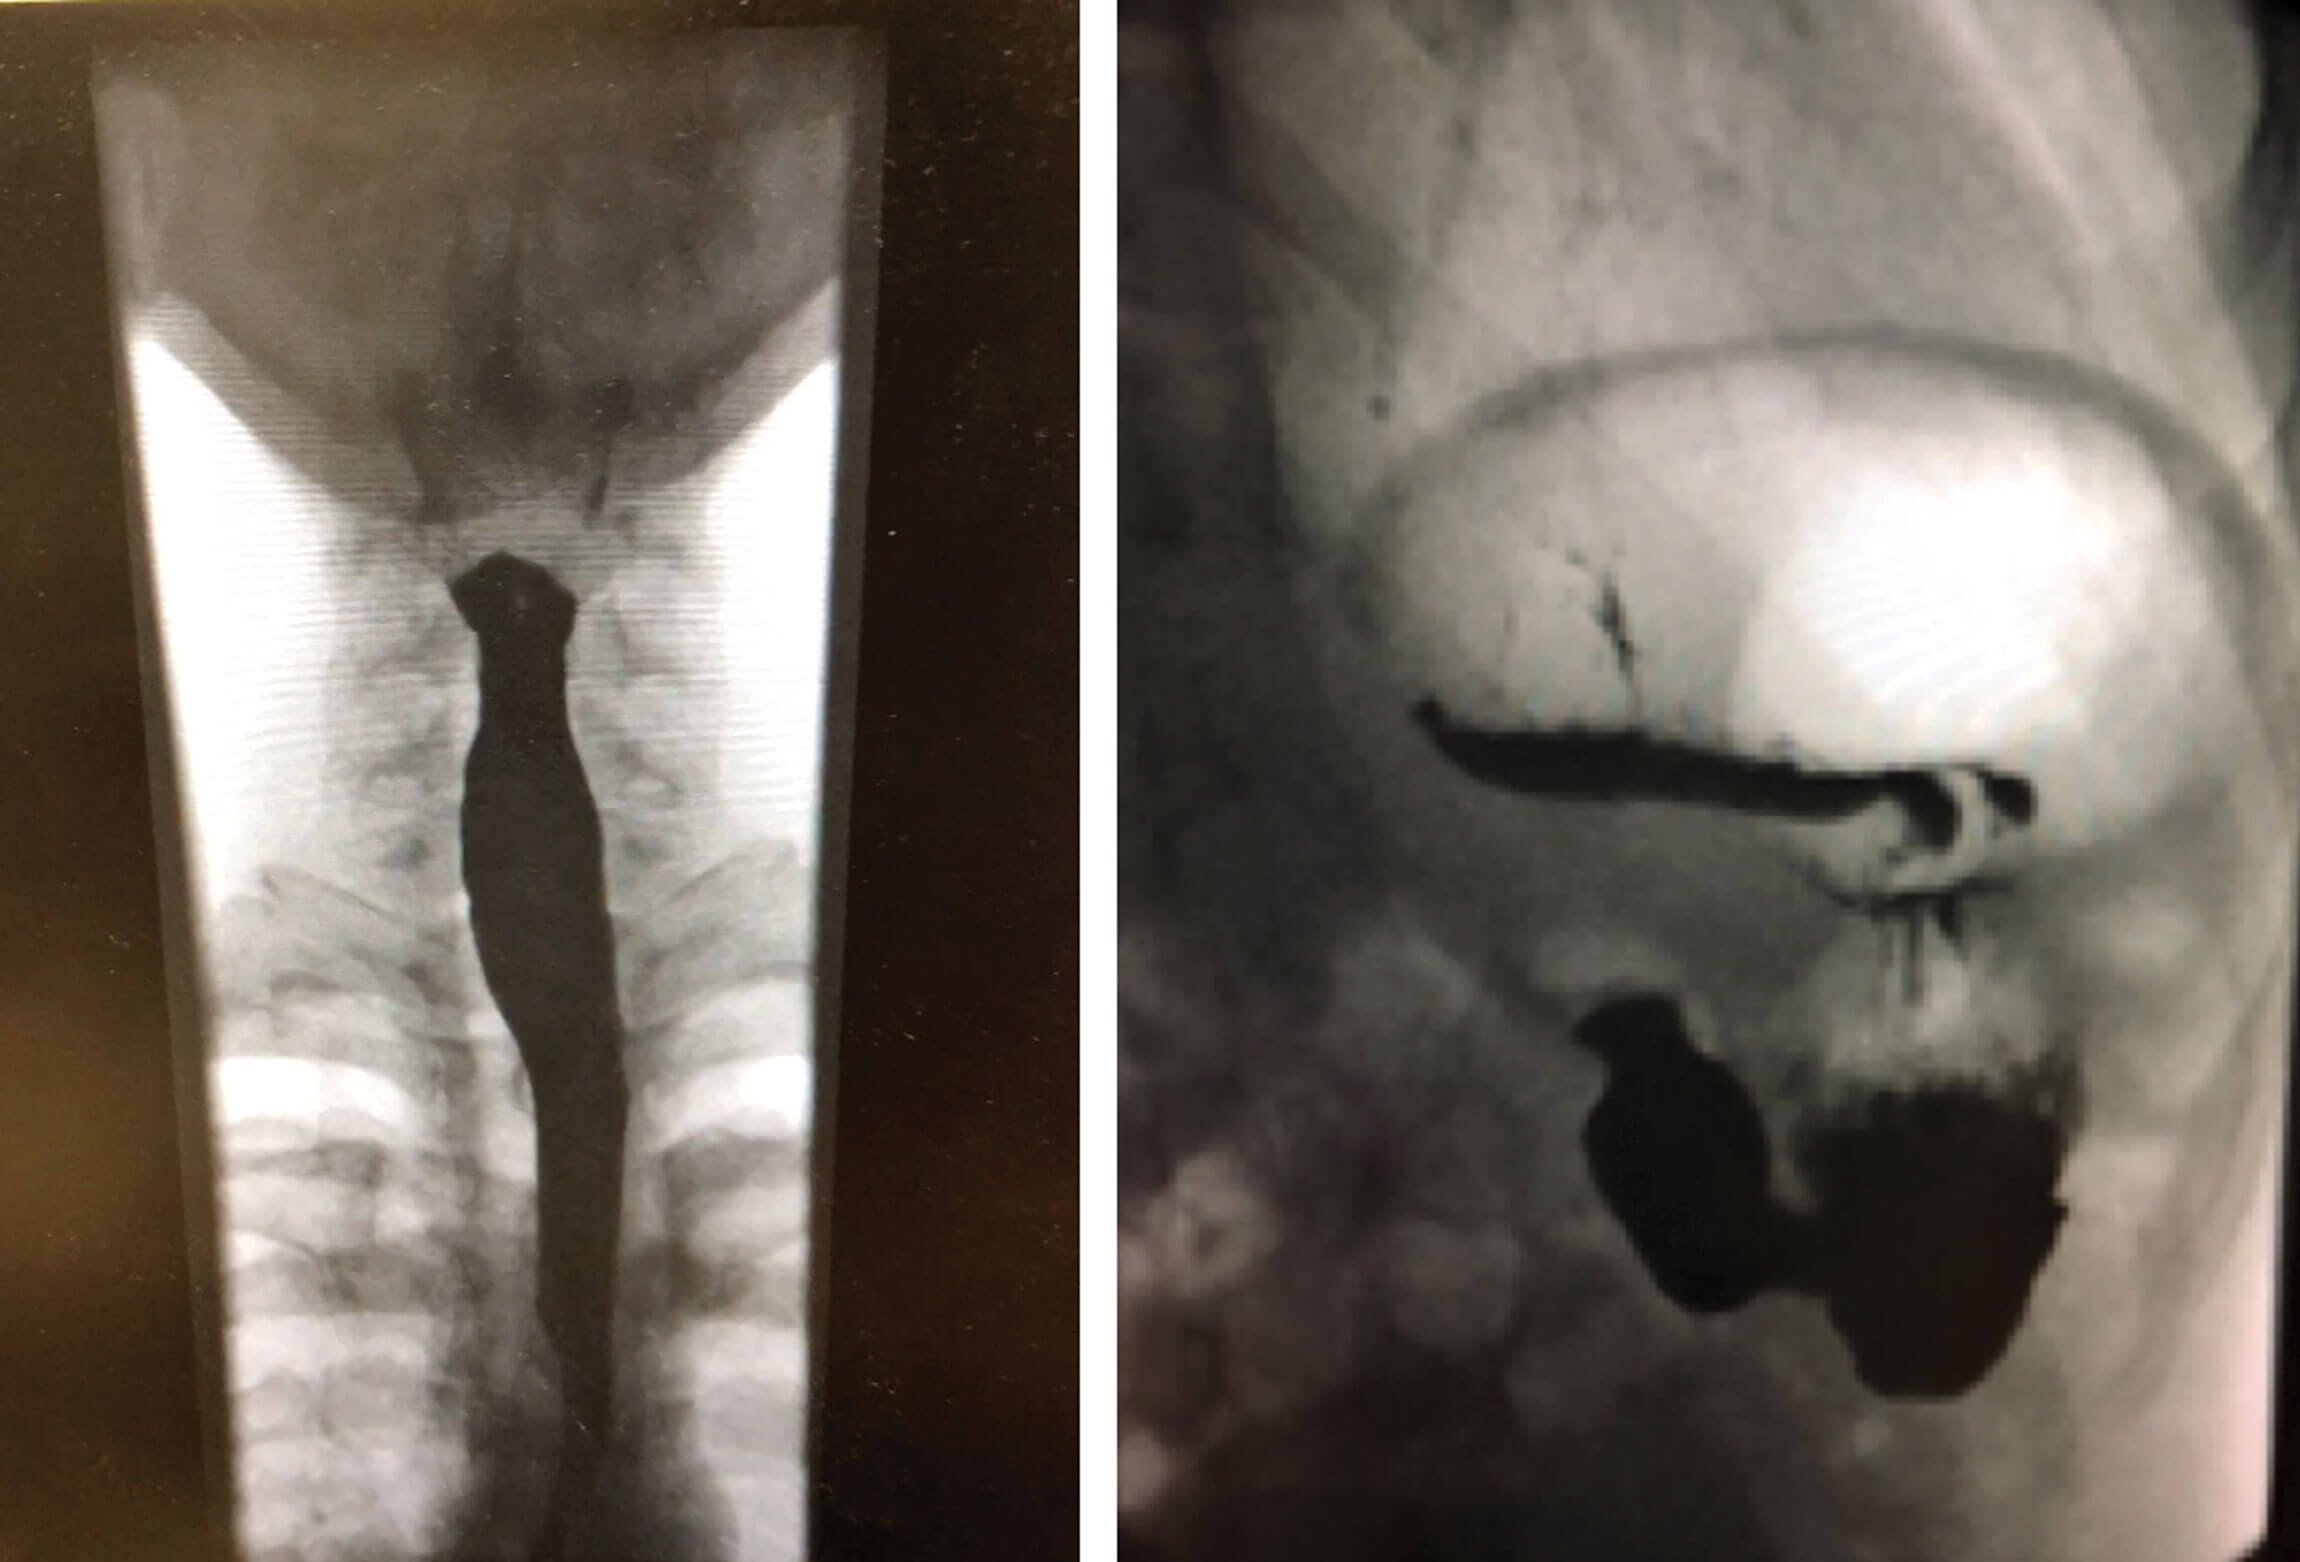

Oesophageal impedance and manometry may or may not show high upper oesophageal sphincter pressure and does not exclude or confirm the diagnosis. Barium swallow may only show gaseous distension of the oesophagus or stomach (Figure 5). Imaging such as USS, CT scan and MRI scan are not necessary as it will often be reported normal but may show gaseous distension of the digestive tract.

Figure 5. Barium swallow showing gaseous distension

of oesophagus (left) and stomach (right).